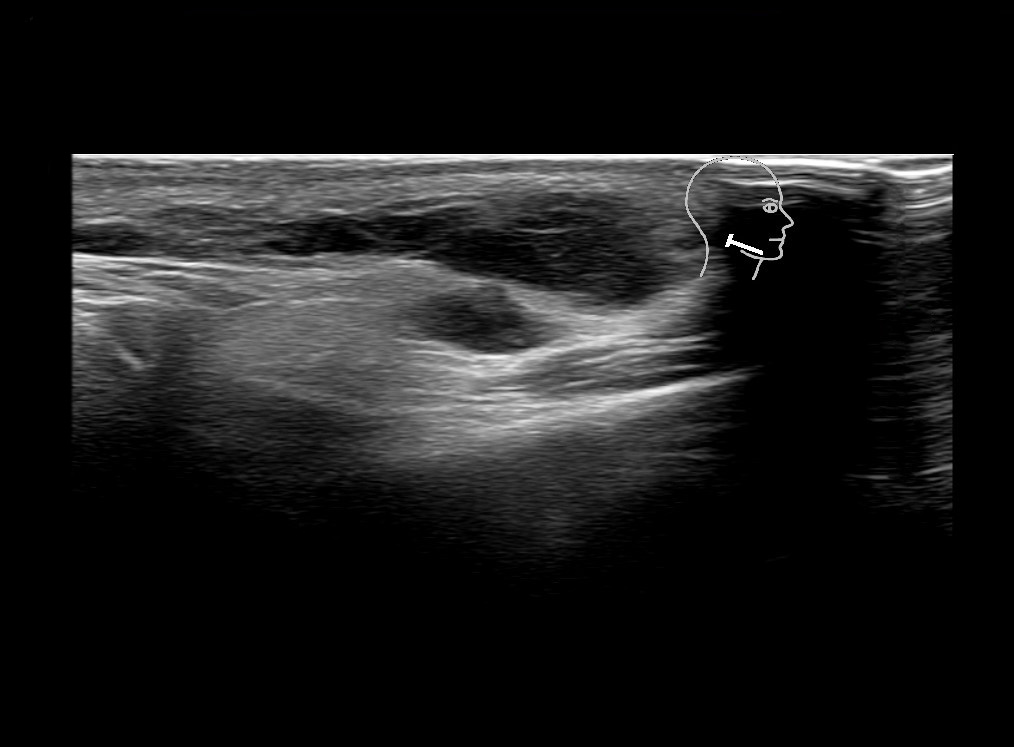

Filler injections in the parotid gland may go unnoticed, however, inflammatory reactions and abscesses may occur. Hypervascularity can be seen with color doppler. Filler deposits are supposed to be injected into the superficial fatty layer . The space to inject into this layer may be limited. Routinely we measure a width of 2-4 millimeters with sometimes subcutaneous layers being less than one millimeter thick.

Study the first image to recognize the different layers. If you are sure about the layers, swipe to the second image to view the answer (if applicable).